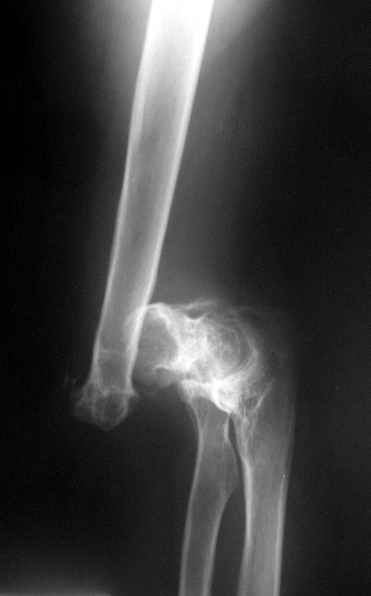

The recent x rays show established Non union with poor quality bone in the distal fragement. The joint is also appearing degenerate. In view of the multiple failed reconstructive surgeries, an Elbow replacement would seem reasonable.

However it would have to be a fully constrained one as there would be missing bone stock.

Obviously there is no elbow joint...the options are few: (from the worst to the "best"...if any)

1. Arthrodesis - last choice if at all

2. If no pain leave it as it is

3. Total elbow replacement (semi constrained - as no ligaments to stabilize the joint) - Coonrad-Morrey, Discovery - Biomet - considering his age there is limited indication for that procedure.

4. There is limited experience with total elbow allograft replacement with some rate of successes on one hand and high rate of complications on the

other hand. I personally would try this option as it is a reversible procedure and one could in a case of failure to replace it with prosthesis